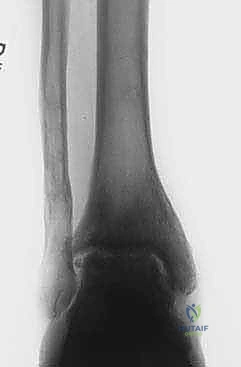

- الأشعة السينية (X-rays) مع الوقوف: لتقييم المسافة المتبقية من المفصل وتحديد درجة الخشونة ومحور الساق.

- الأشعة المقطعية (CT Scan): للحصول على صورة ثلاثية الأبعاد للعظام، واكتشاف أي تكيسات عظمية (Bone cysts) أو نتوءات عظمية (Osteophytes).

- زيادة مساحة المفصل: تظهر الأشعة السينية بوضوح اتساع المسافة بين عظام الكاحل، وهو دليل قاطع على تجدد النسيج الغضروفي.